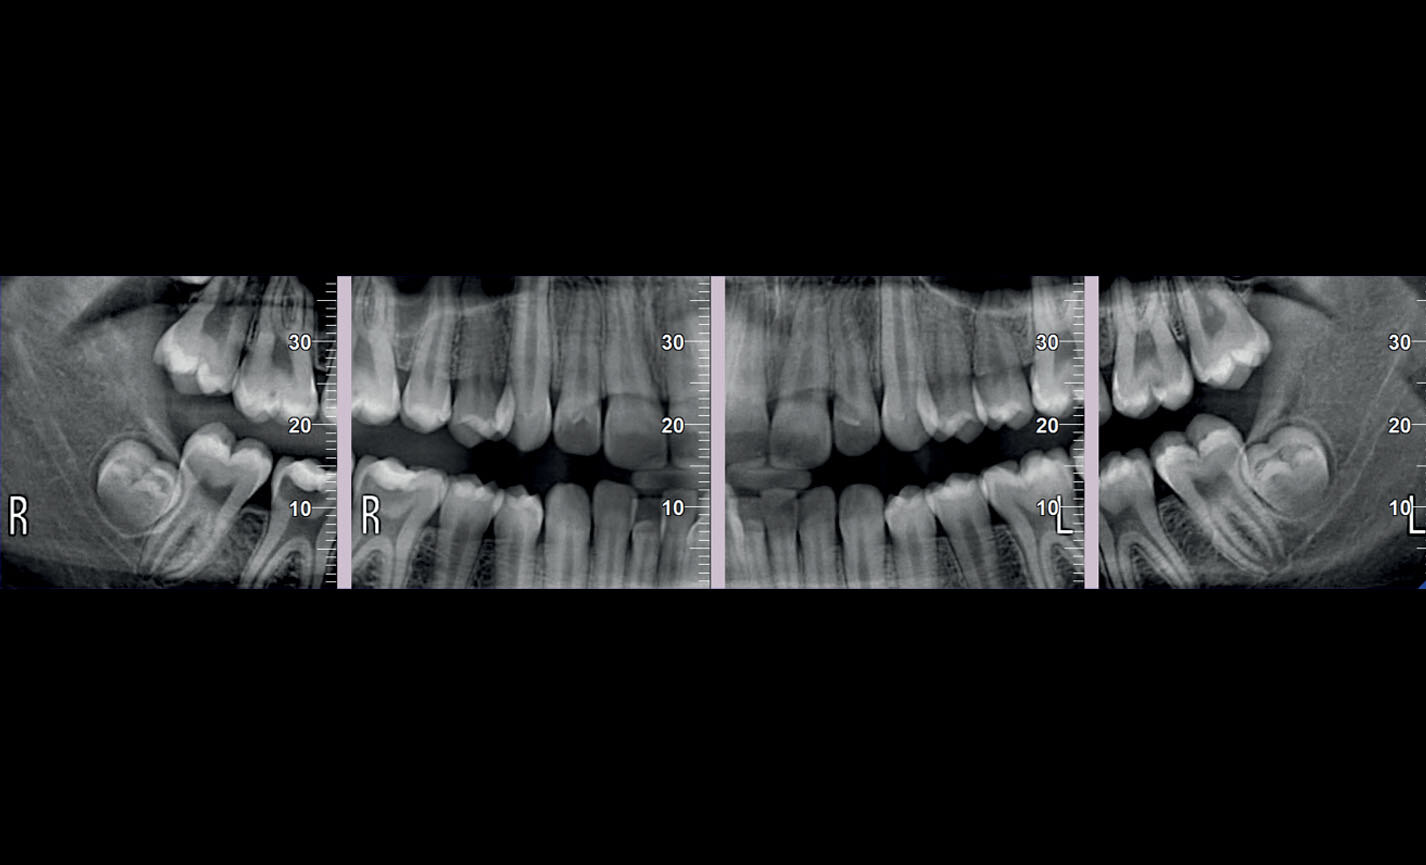

Orthopanoramiques

Panoramique orthogonal : minimise les superpositions d’éléments dentaires adjacents pour une meilleure analyse parodontale.

Orthopanoramiques

Panoramique enfant : exposition limitée et paramètres optimisés pour une investigation pédiatrique rapide.

Orthopanoramiques

Dentition complète à quadrants : investigations localisées avec segmentation sélectionnable pour limiter la dose d’irradiation.

Orthopanoramiques

Projections bitewing, investigation limitée aux couronnes : haute résolution et faible dose, une alternative valable aux images intra-orales en cas de patients avec un fort réflexe de rejet.

Applications orthodontiques

Des FOV de 10 cm de diamètre sont nécessaires pour l’étude des troisièmes molaires incluses car, chez un adulte de taille moyenne, la distance entre les troisièmes molaires de droite et de gauche, en incluant leurs racines respectives, le processus alvéolaire et l’os avoisinant, est d’au moins 9 cm. Les champs de vision réduits sont utiles en cas d’analyse de dents incluses ou surnuméraires, pour limiter la dose à la seule région d’intérêt. En effet, pour une planification correcte du traitement, il est fondamental de déterminer la position réelle (vestibulaire ou palatine), possible uniquement avec une analyse 3D, même à très faible dose avec un protocole QuickScan. Le champ de vision complet 13 x 16 cm permet une évaluation minutieuse des voies aériennes supérieures, souvent utile pour compléter une investigation en vue d’un traitement orthodontique qui tienne compte des problématiques oto-rhino-laryngologiques.